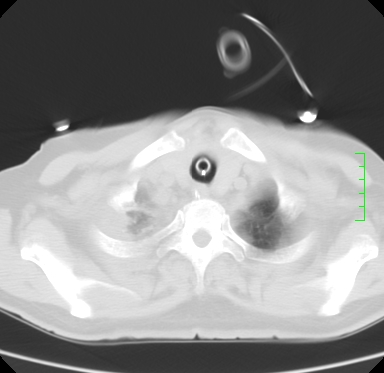

icu病人,几天都没明确诊断。m,76y,咳嗽、咳痰1周,伴气促,右胸痛入院,pe:t38.3c p135 r25 bp135/85。双肺可闻及大量湿罗音,心、腹未见明显异常。诊断:1心衰?2肺部感染?3冠心病?

9号平片